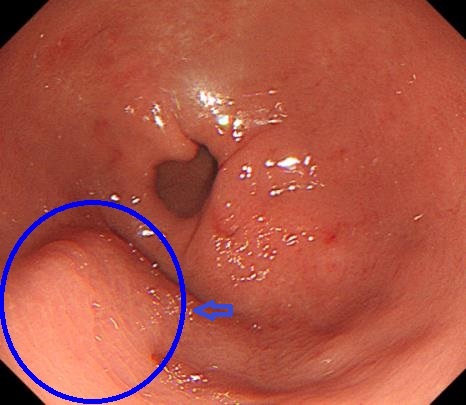

胃镜:胃窦大弯隆起

5天前,王女士误服枣核,之后出现上腹部隐痛,进行性加重,并伴有发热、恶心等症状,自服多种胃药治疗,症状未改善。来院就诊行胃镜检查提示:胃窦大弯侧见一约1.5cmX1.0cm的广基隆起,表面粘膜光滑。进一步行超声内镜扫查显示:胃壁第2、3层内见一椭圆形混合回声区域,边界清晰,切面大小约1.0cmX0.5cm,结合病史,确诊为胃脓肿。